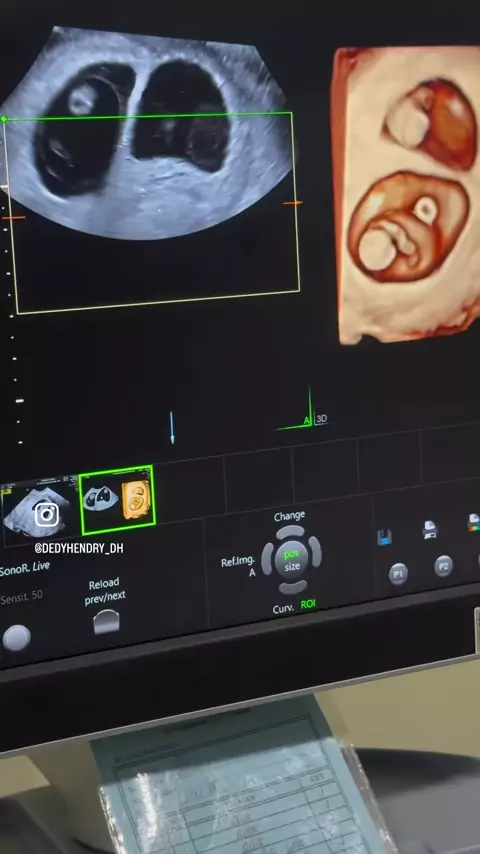

Alhamdulillah bertubi-tubi dapat kembar lagi raport IVF tgl 03/10-2024 pada pejuang endometriosis pasca laparoskopi kista endometriosis bilateral dan endometriosis tuba serta PCOS pada tahun 2023, terapi hormon 6 bulan lanjut bayi tabung .. transfer 2 embrio alhamdulillah menempel keduanya jadi hamil kembar.. Alhamdulillah ya Allah semua atas ijin dan karunia Mu yang begitu besar.. Allah maha kuasa makluk tak kuasa” @klinikdesani @Morula IVF Padang

hamil usia 42 tahun tidak mudah ya alhamdulillah atas ijin dan kuasa Allah.. bisa terhindar dari embrio an euploid dan kehamilan blighted ovum (BO) pada usia lanjut.. merupakan anugrah terbesar.. Alhamdulillah @klinikdesani @Morula IVF Padang

Alhamdulillah hamil lagi😇😇 kasus : PCOS + Cryptozoospermia Penantian 10 tahun.. @klinikdesani @Morula IVF Padang #infertility #ivf #ivfsuccess #bayitabung #pcos #edukasidokterdedy #praktekdokterdedyhendry #klinikdesani

alhamdulillah atas ijin Allah 2 bulan ini yaitu Juni-awal juli angka kehamilan bayi tabung cukup tinggi pada pasien2 yang secara kondisi klinis cukup sulit karena faktor usia yang lanjut, cadangan telur yang rendah, endometriosis, adenomiosis, tapi alhamdulillah atas ijin dan pertolongan Allah menurunkan rahmat dan karunia Nya pada orang yang dikehendaki Nya.. Alhamdulillah @klinikdesani @Morula IVF Padang